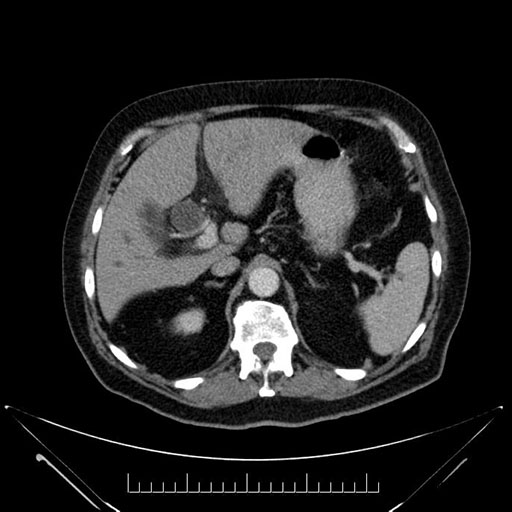

Imaging Analysis

Look through the patient's CT scan to identify any areas of concern for the necessary procedure.

Based on your CT findings, which issue(s) would give reason for "planned slowing down moment(s)" in this case?